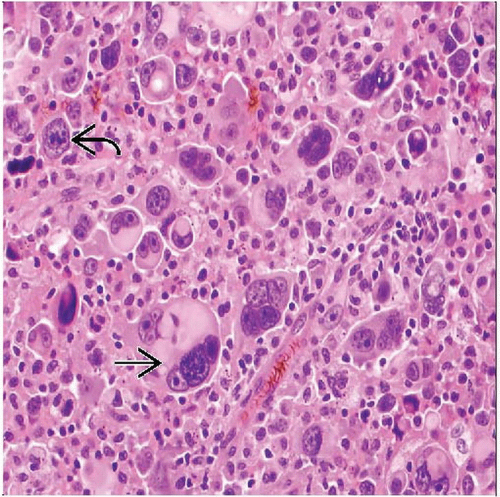

Pleomorphic Rhabdomyosarcoma | Basicmedical Key

basicmedicalkey.com

basicmedicalkey.com

rhabdomyosarcoma pleomorphic